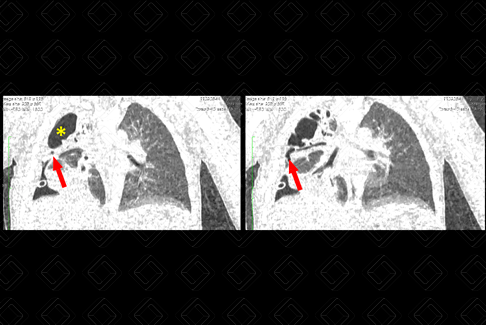

Texto alternativo para a imagem Créditos: Dra. Elazir Mota - Rio de Janeiro/RJ

Descrição da figura: Paciente 2 anos, com diagnóstico de pneumonia necrotizante, evoluindo no D28 de dreno torácico, sem melhora. Realizou tomografia computadorizada do tórax para melhor avaliação, sendo diagnosticado com fístula broncopleural. Observe nas setas vermelhas, o brônquio subsegmentar dirigindo para o pneumotórax direito (asterisco amarelo).

• Tomografia computadorizada do tórax: Idealmente deve ser realizada após a administração do contraste venoso. A tomografia é um método excelente para esta avaliação pela sua capacidade de realizar reconstruções multiplanares (figura acima). Algumas das suas ferramentas podem ser utilizadas, como projeções em mínima e máxima intensidade (Mip e Minip) e a broncoscopia virtual.